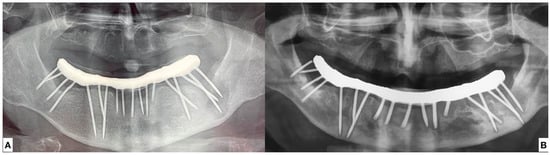

2.1.1. Surgery Appointment (September 2021)

2.1.3. Follow Ups and Implants Insertion

- surgical insertion of two anterior implants in the region of the mandibular canines

- rehabilitation with implant-supported OVD adapting the current complete removable denture, 3 months after implant surgery.

3.1. Case Report